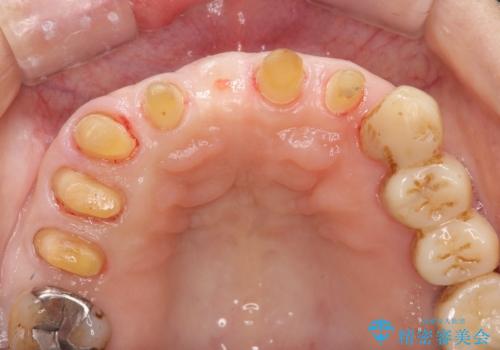

歯周病に対する全体治療

- 近医で「重度の歯周病です、入れ歯にする必要がある。」、と言われ入れ歯以外の方法がないか相談にみえられました。

再生治療、歯周外科を行うことで歯周病治療を行い、残すことのできる歯の歯周環境を整える。

残すことのできない歯は抜去したのち骨造成を含めたインプラント治療を行い、しっかりとした咬合関係を確立していきます。

治療期間はかかりましたが、しっかりと歯周病治療・インプラント治療を行ったおかげで歯周病の状態は非常に良くなり、安定した咬合関係を確立することができました。